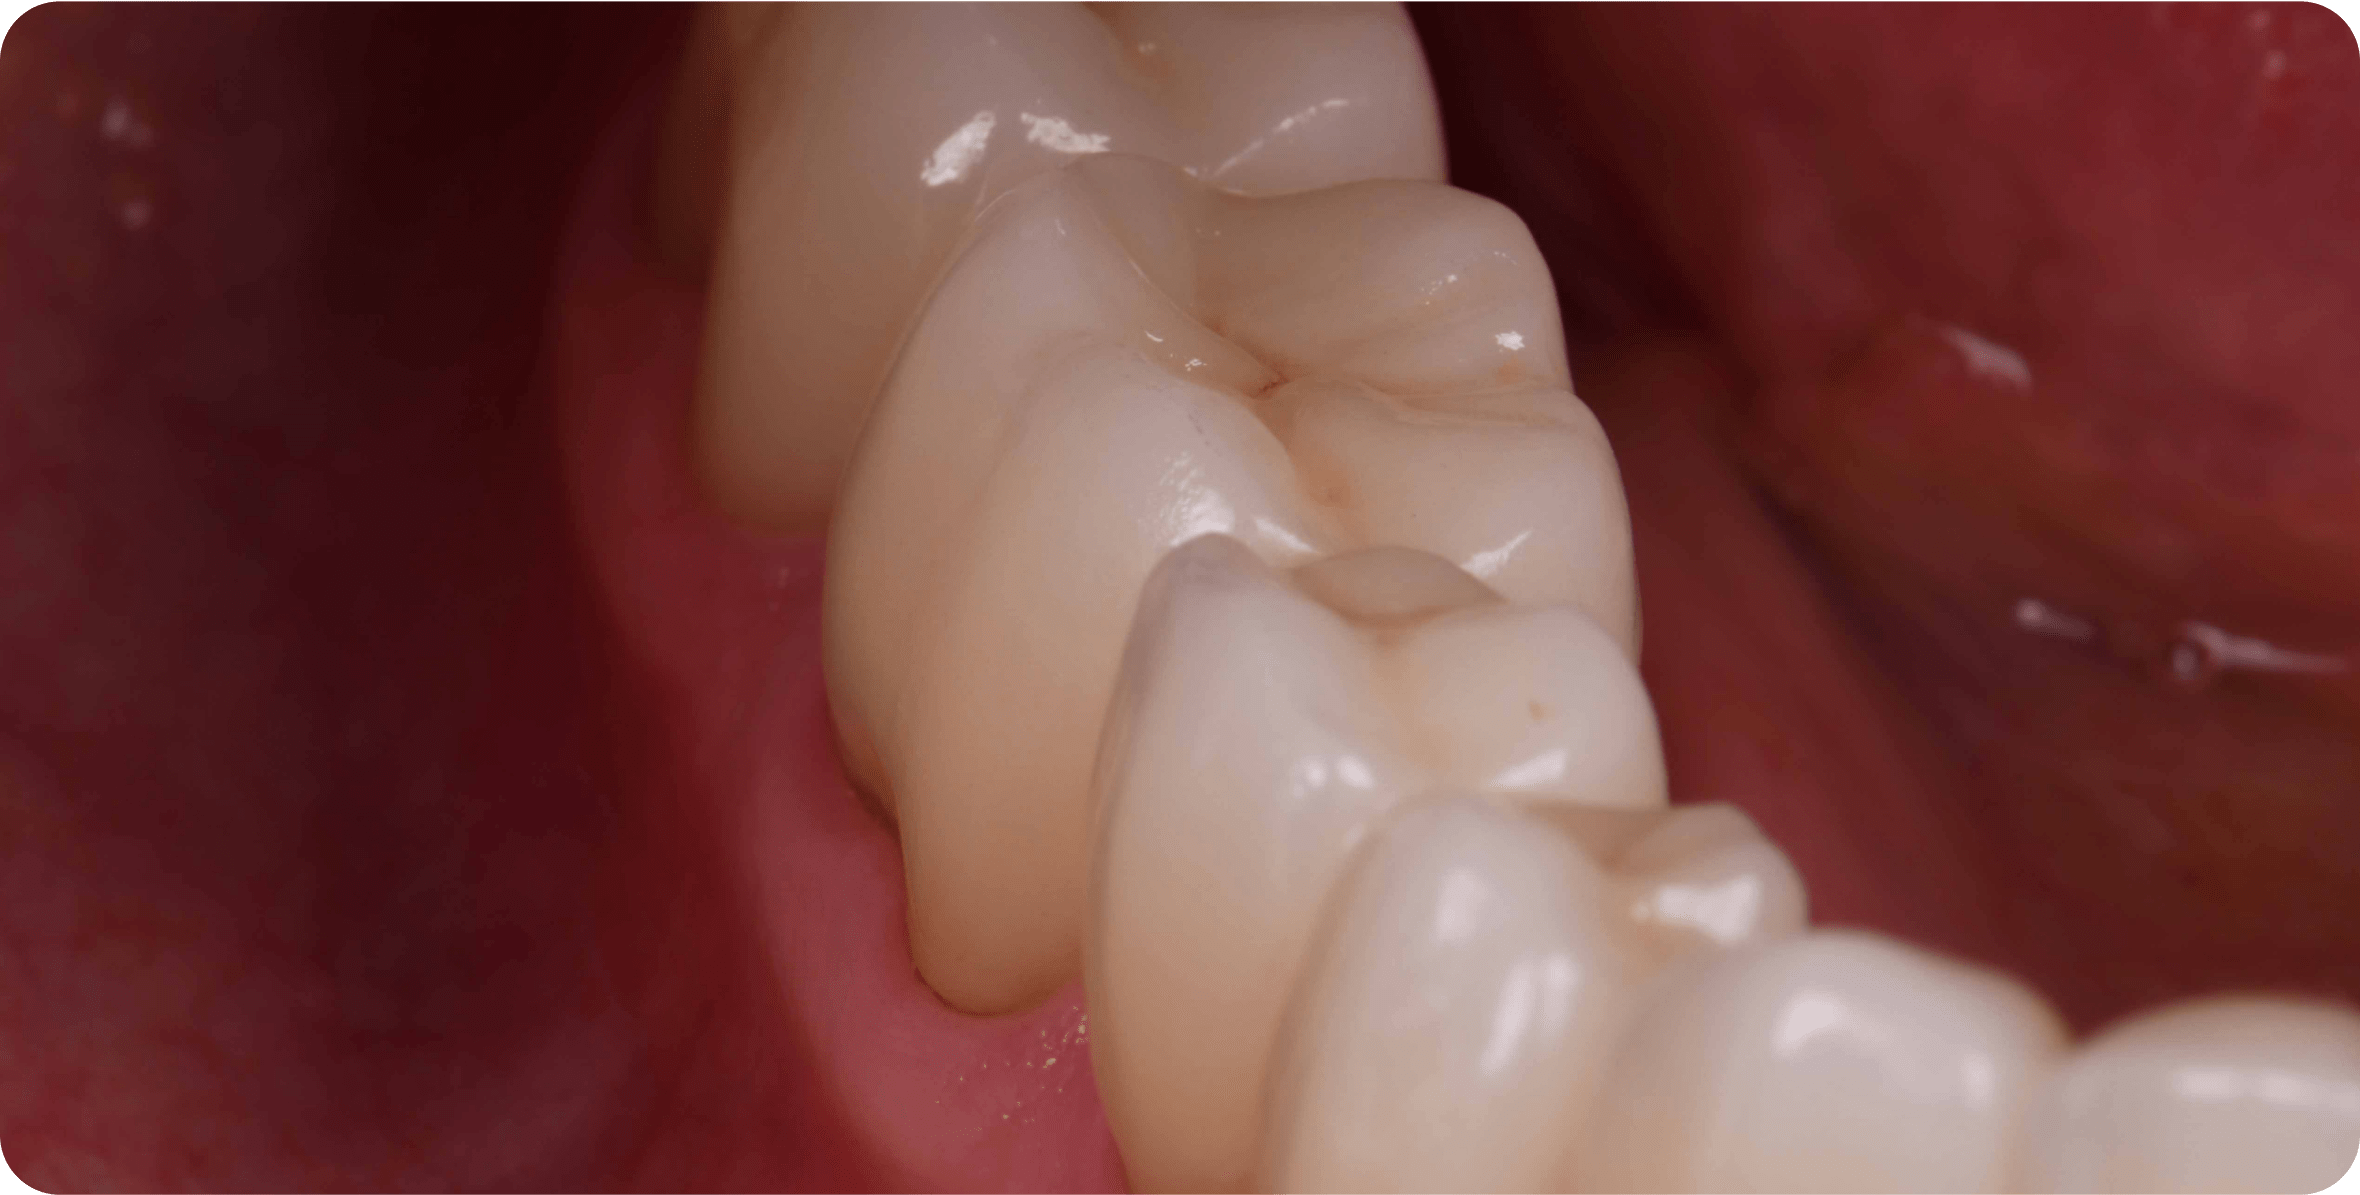

Лечение каналов (удаление нерва зуба) необходимо, когда кариес слишком глубоко проникает в зуб и поражает сосудисто-нервный пучок

Основная цель лечения каналов - сохранить корень зуба от разрушения

Стоматолог-терапевт удаляет воспаленный нерв, прочищает каналы зуба и заполняет пломбировочным материалом, а сверху устанавливает пломбу или коронку